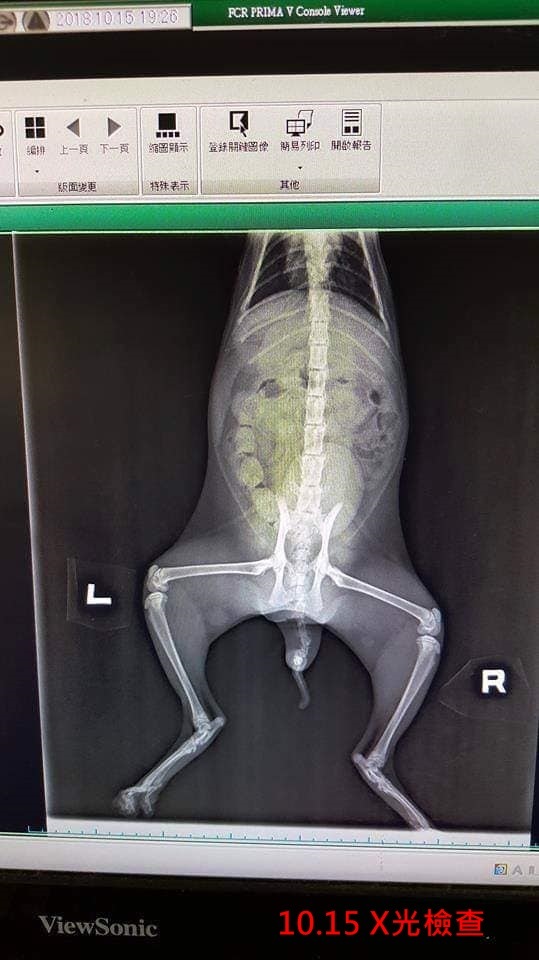

今年10月間工作人員前往時發現了一隻虎斑小母貓咪,左後腳疑似受傷,走路時無法著地,也還未進行結紮,於是在10月14日先將小母貓咪帶回協會,翌日送往醫院進行檢查。

醫師於小母貓咪麻醉結紮同時仔細檢查腳部及X光檢查,幸好骨頭未受傷,但腳掌趾間皮膚有紅腫,研判是濕疹導致感染使腳掌腫起。

10月15日:入院,結紮、X光檢查。